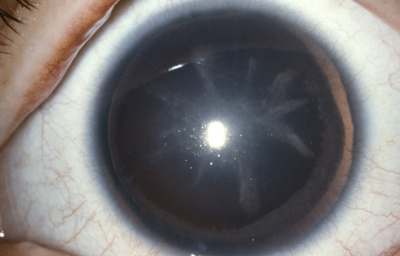

Aniridia completa, catarata y distrofia corneal de la aniridia

Archivo Dr. Francisco Barraquer

Caso de paciente con Coloboma en un ojo y Aniridia en el contralateral

OD

Archivo Fotográfico Dr. Francisco Barraquer

OI

Archivo Dr. Francisco Barraquer